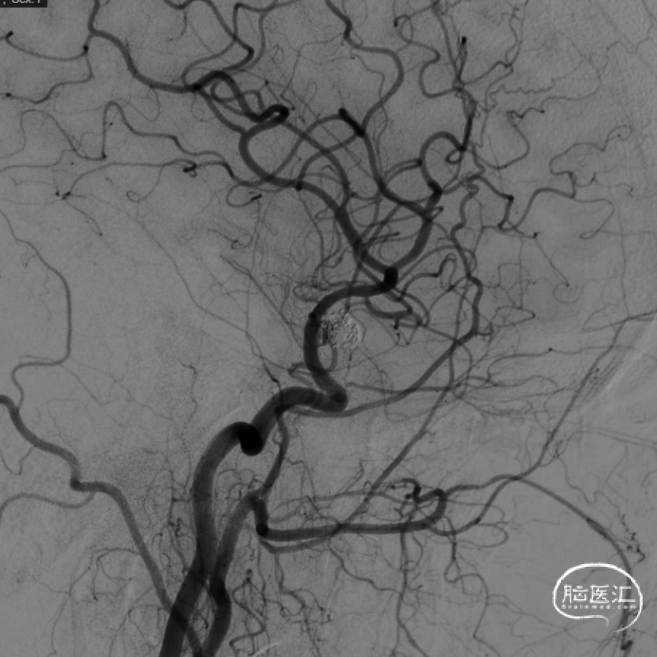

术后即刻工作位造影显示,支架全程打开形态良好,充分贴壁。

术后即刻正/侧位造影显示:各分支血管血流通畅,无出血情况,瘤体内无造影剂充盈。

术后3D造影:支架打开充分,全程贴壁,各分支血管血流通畅,可看到内翻的Mark点也被Evolve贴到了血管壁上,充分体现了Evolve足够强的径向力,预示着Evolve对动脉瘤合并狭窄应用或许是一个不错的选择。